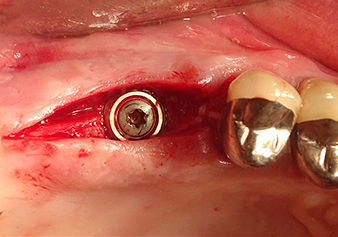

Situation after insertion of the implant

Fig.9: Situation after insertion of the implant (length: 10 mm, prosthetic platform: 6.5 mm) immediately before suturing.

Implantation and prosthetic restoration

To move the augmentation material in the direction of the maxillary sinus atraumatically, the implant was inserted very slowly by hand (Fig. 9). In the process, the membrane was pushed in the cranial direction once again. After two months, the surgical site healed without irritation. Six months later, the x-ray check showed a significant increase in opacity as an indication of ossification (Fig. 10). The prosthetic restoration was carried out with a metal-ceramic crown.